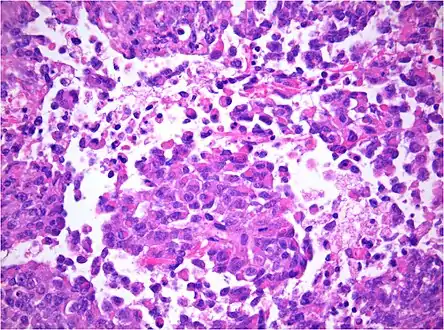

Histology

The tumor histopathology is jumbled small and large cells. The tissue of this tumor contains many different types of cells including the rhabdoid cells, large spindled cells, epithelial and mesenchymal cells, and areas resembling primitive neuroectodermal tumor (PNET). As much as 70% of the tumor may be made up of PNET-like cells. Ultrastructure characteristic whorls of intermediate filaments are seen in the rhabdoid tumors (as with rhabdoid tumors in any area of the body). Ho and associates found sickle-shaped embracing cells, previously unreported, in all of 11 cases of AT/RT.[18]

AT/RT and rhabdoid tumor share the term "rhabdoid" because under a microscope, both tumors resemble rhabdomyosarcoma.